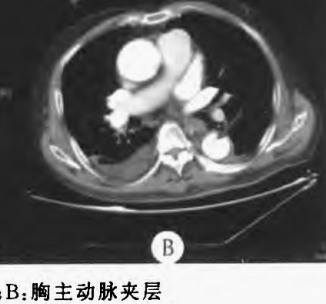

下图的胸部CT平扫,有什么大问题?

图4

仔细一看,主动脉里面有线样高密度阴影!这个要高度警惕主动脉夹层!

图5

增强CT一看,吓到一大片!太惊悚了!

图6